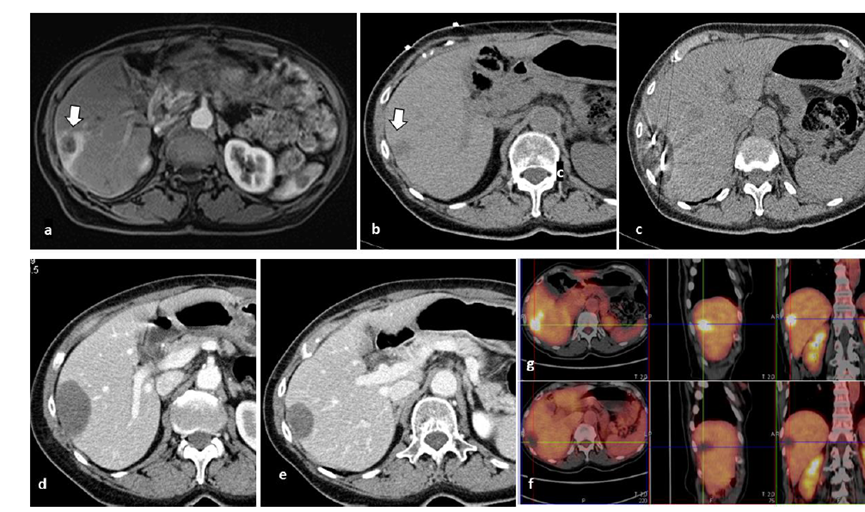

CT引导下冷冻消融

79 岁男性,肝转移(结直肠癌)肿瘤的完全消融病例

( a ) 轴向 MRI 和 ( b ) 轴向 CT 显示肝S8段有一个16mm的病灶,邻近肝缘。

( c )冷冻消融期间CT显示放置了2个冷冻探针,低密度冰球包围病灶。

(d)术后1个月随访 CT显示冰球对应的坏死区域,未见复发。

(e)术后6个月的CT,坏死区域缩小,未见复发。

(f)与基线影像(g)相比,12个月后的FDG-PET/CT显示未见FDG摄取。